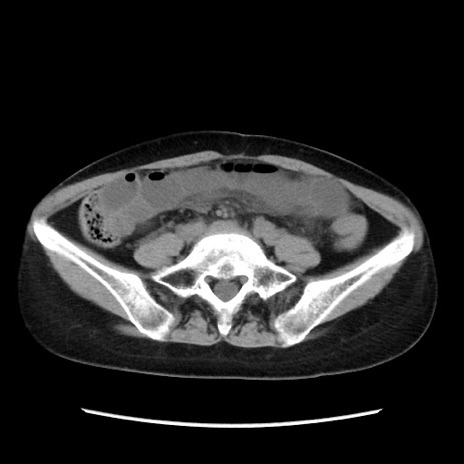

症例32(横断像)

【症例】40歳代 女性

【主訴】上腹部痛、嘔気・嘔吐

【現病歴】約9時間前頃から急に上腹部痛、嘔気、嘔吐が出現。改善しないため救急要請。

【既往歴】子宮頚癌(広汎子宮全摘術、放射線療法)、腸閉塞

【身体所見】腹部:平坦、軟、腸雑音亢進、上腹部を中心に腹部全体に圧痛あり。

【データ】WBC 8400、CRP 0.03